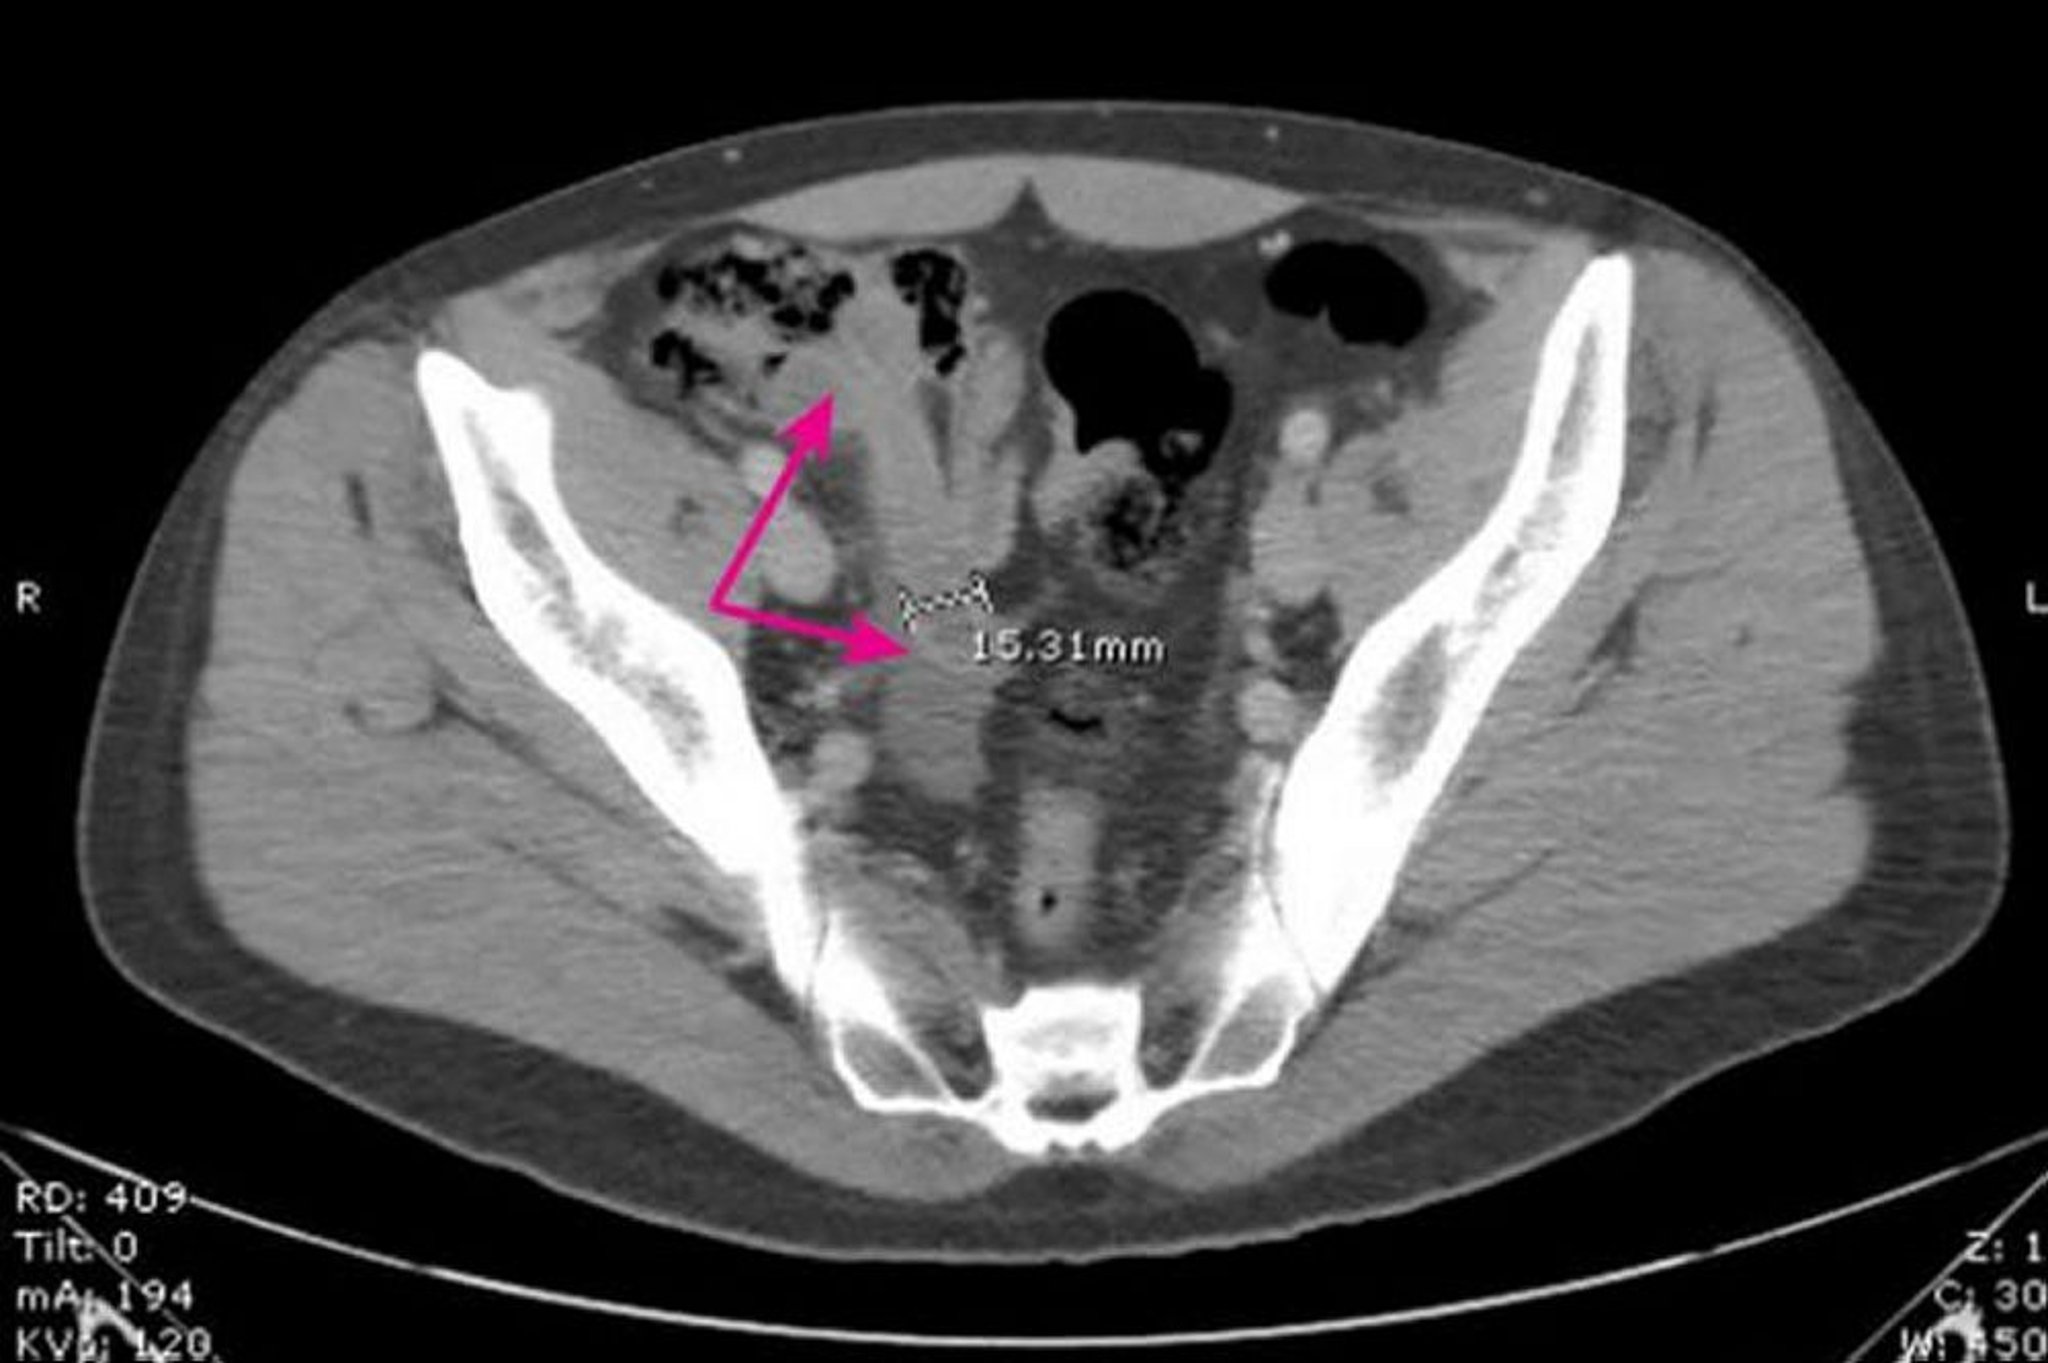

Essa imagem mostra um apêndice dilatado de paredes espessas (setas) medindo 15,31 mm de diâmetro com alterações inflamatórias circundantes.

Image provided by Parswa Ansari, MD.